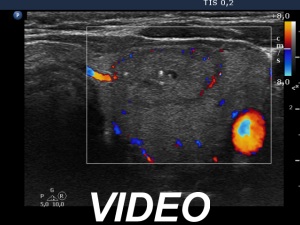

A single bright echogenic focus within the right nodule can be seen in the video. This figure belongs to punctate echogenic foci subgroup.